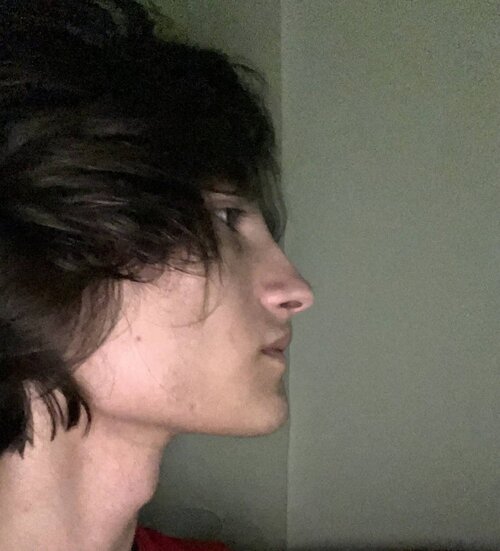

I need some advice! I have a deep and distal bite, and I've been thinking about bimax or lefort surgery, but my orthodontist said that it can be fixed with braces without surgery. The plan is to move the upper teeth slightly back and the lower teeth slightly forward to correct the bite, but I'm worried that moving the upper teeth will also move my maxilla, which is already flat. Should I be concerned about this? I want to receive valuable advice from experienced and knowledgeable individuals.

Rhino ik, Here's a photo:

I can take any necessary measurements of the bones.